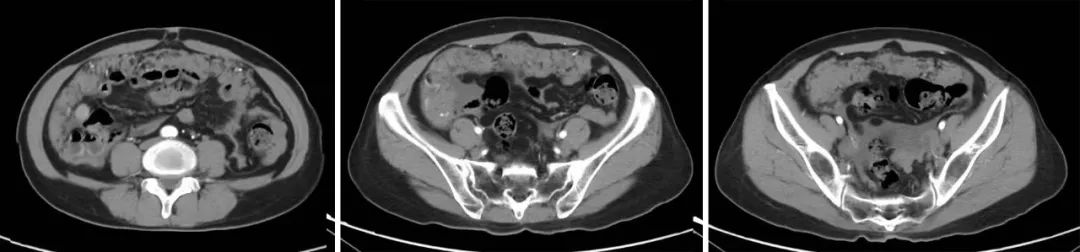

51岁女性恶性腹膜间皮瘤患者,在经过多手段联合治疗后已存活四年,且生活质量如常人。

该患者在4年前经穿刺活检确诊恶性腹膜间皮瘤,经系统性全身治疗后病情仍进展,出现乏力、恶心、呕吐、腹痛等症状,检查提示广泛腹膜病变,大网膜病变尤其明显,呈大饼状覆盖在胃肠道表面,合并血性腹水。患者全身状况较差,存在营养不良、贫血、水电解质紊乱、感染等情况。为了更好地控制病情,患者在对症支持治疗的基础上,接受了经动脉导管灌注化疗联合载药微球栓塞治疗(D-TACE)、腹腔热灌注综合治疗及靶向药物治疗。经上述治疗后,患者肿瘤负荷明显减小,病情逐渐好转,稳定后采用抗血管生成药物、中成药维持治疗。为了进一步控制病情,患者于今年4月接受了肿瘤细胞减灭术治疗,术后采用相关治疗,目前恢复良好。